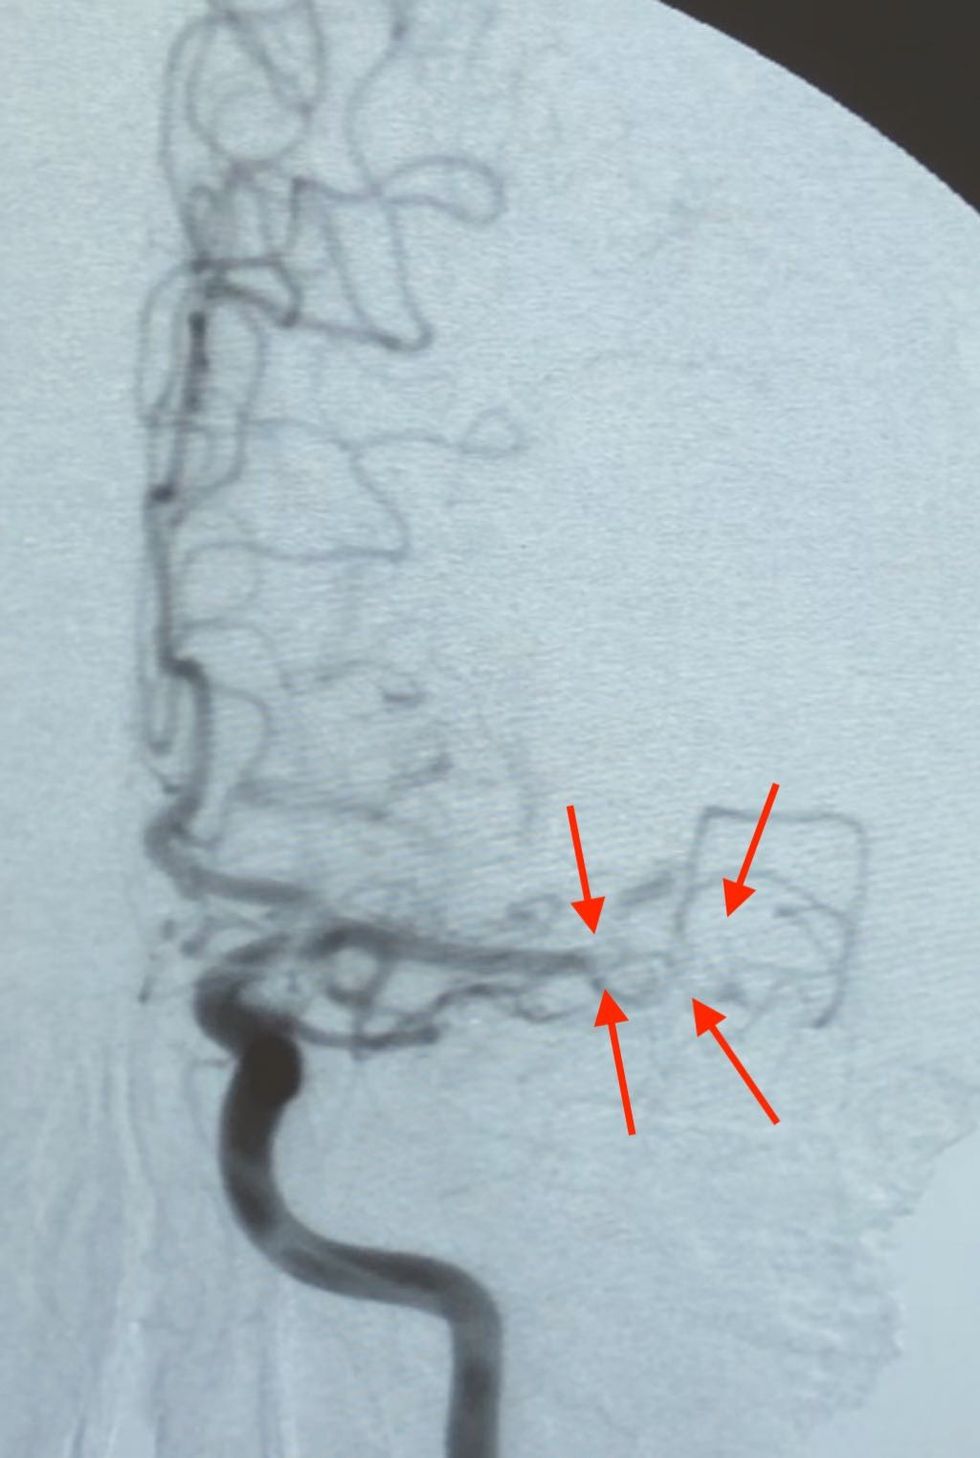

Në imazhet e ADS rekanalizim i arteries trurore të mesme majtas (ACM).

Post procedural, pacientit i rikthehet aftësia për të folur dhe lëvizur trupin.